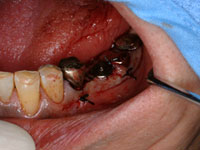

術前の写真です。

埋入直後の写真です。

鏡面像。左右が逆になります。埋入から3ヶ月後、インプラント体に上部構造(歯の部分)を装着します。

鏡面像。左右が逆になります。上部構造(歯の部分)を装着しました。なんでも噛むことができるようになります。